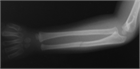

1. 尺骨骨折があった場合、橈骨頭脱臼を見流さないことがポイントである。

1. 見逃された陳旧例では前腕の回旋運動と肘の屈伸運動が障害される可能性があるため、できるだけ早く専門医に紹介する。